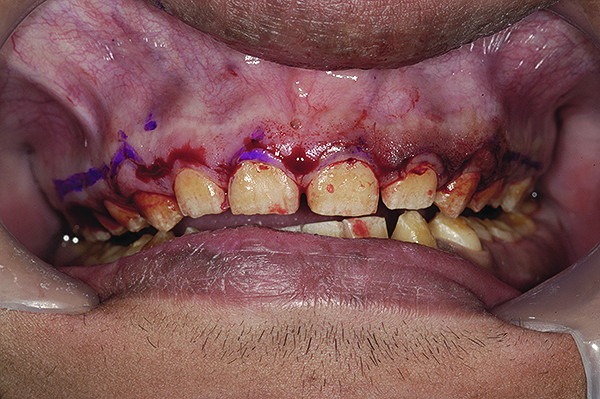

Figure 9. Marking gingival levels during crown lengthening.

Figure 9

Esthetic Repositioning of Gingival Tissues

After administering local anesthesia, a periodontal probe was used to sound the bone on facial and interproximal aspects of all upper teeth. With the upper cuspids and bicuspids, there was insufficient distance between the proposed free gingival margin and the crestal bone (< 3 mm) (Figure 9). In such circumstances, merely trimming the gingival tissues without altering the bone could lead to a violation of biologic width, with its associated complications, one of which is the rebound of gingiva to its original level. Thus, for these teeth, an osteoplasty, along with gingival resection, was carried out. On most other teeth, including the lower anterior and posterior teeth, a gingivectomy was sufficient to achieve correction of gingival levels and proper width-to-length ratios of teeth.

An aspect of crown lengthening in cases of AI is to leave the gingival margins at the cementoenamel junction (CEJ) of the teeth. This is done so that any defective and pitted enamel is exposed and tended to in the final restorative design. Failure to do this may lead to recurrent gingival ill-health due to plaque accumulation in the pitted surfaces. In this case, however, upon raising the mucoperiosteal flap, it was found that the CEJ was missing as a result of total absence of enamel. Thus, the gingival margins were placed at the desired esthetic levels and sutured with monofilament sutures (Figure 10) and reevaluated after a healing period of 4 weeks (Figure 11).